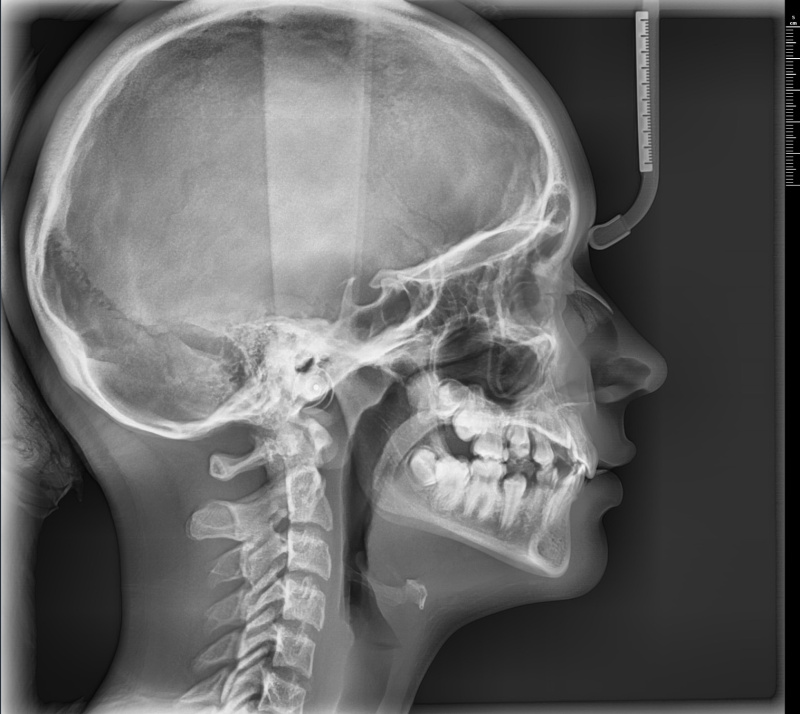

Dokładne obrazy 2D i 3D – niezbędne w chirurgii, ortodoncji, endodoncji i laryngologii

Zakres obrazowania – od pojedynczego zęba po całą czaszkę

Nowoczesna tomografia 3D twarzoczaszki – zębów, kości, zatok i stawów. Badanie jest szybkie, bezbolesne, a skan trwa zaledwie 2,9 sekundy.